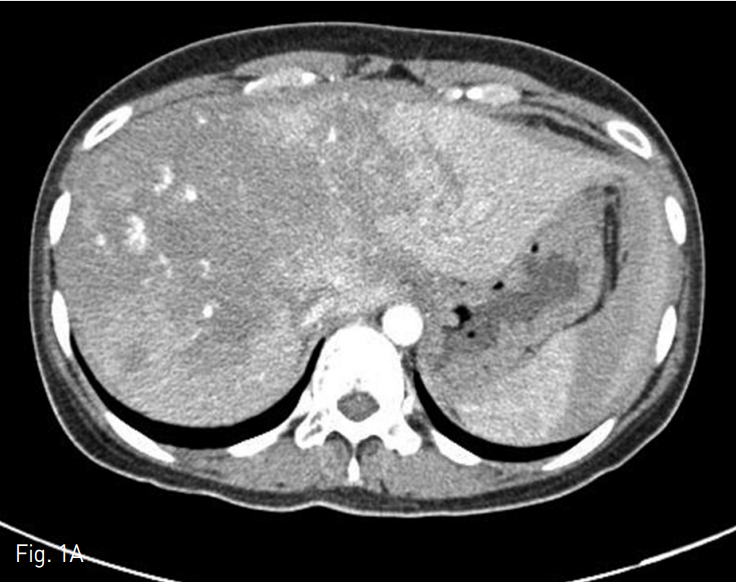

혈관조영술과 색전술을 위하여 우측 총 대퇴동맥을 통해 5 Fr RH catheter를 간동맥에 위치시킨 후 카테터 내에 2.2 Fr 미세도관을 삽입하여 다발성의 점상출혈이 있는 부위에 대하여 gelatin particle을 이용하여 색전술을 시행하였다. 색전술 시행 다음날, 다시 복부팽만과 hemogloin 수치 감소(8.8g/dL → 8.0g/dL)가 발생하여 복부 CT를 시행하였다. 추적 복부 CT상 간 내 혈종의 양이 증가되었고 2, 3번 segment에도 새롭게 다발성의 점상출혈이 보였다 (Fig. 1D). 새로이 보이는 Left lobe의 다발성 점상출혈을 확인하기 위하여 간동맥 혈관조영술을 시행하였으나 명확하게 출혈소견이 보이지 않았기에 간 동맥 외의 다른 동맥을 통한 출혈부위를 찾기 위하여 5 Fr Headhunter angiocatheter를 이용하여 우측 내유동맥의 혈관조영술을 시행하였고 (Fig. 1E, F) 내유동맥 조영술상에서 간 좌분절의 다발성 점상출혈을 확인하고 2.2 Fr 미세도관으로 진입하여 gelatin particle을 이용한 색전술 시행하였다. 이후에 환자는 더 이상의 출혈소견 없이 호전되었다.

D. A follow-up contrast enhanced CT scan showed interval increased large amount of intrahepatic hematoma. And newly developed, pseudoaneurysmal active bleeding foci in segment 4 of liver.